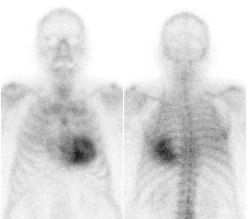

/ Obr. č. 1: „Celotělová“ scintigrafie v přední a zadní projekci. Vyšetření 5 minut po aplikaci radiofarmaka.

/ Obr. č. 3: „Celotělová“ scintigrafie v přední a zadní projekci. Vyšetření 3 hodiny po aplikaci radiofarmaka.

Je patologicky výrazně zvýšená depozice radiofarmaka v myokardu levé srdeční komory (s maximem septálně a minimem posterolaterálně supraapikálně). Zvýšená depozice je mnohem vyšší než v žebrech - dle semikvantitavní škály jde o stupeň 3.